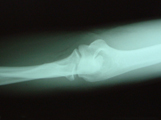

X線所見:上の写真では橈骨頸部の骨折が認められ、やや傾斜した状態の転移が認められました。また橈骨頭部に2ヶ所の骨折が認められました。こちらは、大きな転移は認められませんでした。

この写真は、整復後の写真です。傾斜した転移は十分に正常位置に整復されていることが確認されています。この写真は、8週目(58日目)のレントゲン写真です。骨折部位は治癒と判断されました。